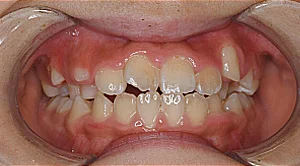

子どもの矯正

成長過程にあるお子さまは、その成長をうまくコントロールして導くことで歯並びと咬み合わせを良くしていくことが大切です。

当院では、お子さまの歯並びが悪い方向に向かっている「原因」は何なのかをきちんと診断し、その改善を図ったうえで、歯並びを整えていく将来を見据えた治療を行なっています。